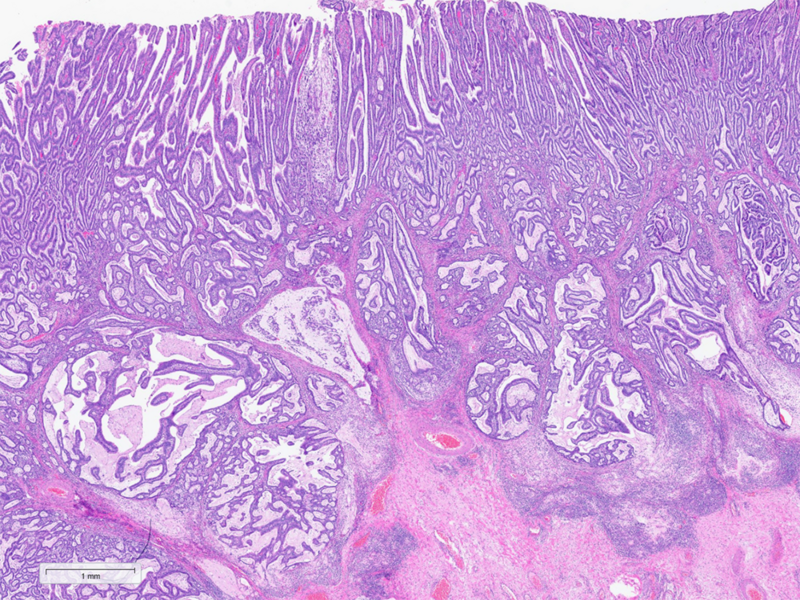

A 92-year-old man diagnosed with gastric cancer underwent a partial gastrectomy. On gross examination, the specimen measured 11×6 cm and a 4.5 cm tumour was identified 2 cm from the distal margin within the antrum.

Histologically, the tumour was confirmed to be an adenocarcinoma invading through the gastric submucosa into the muscularis propria (Panel A), showing multiple architectural patterns. While the majority of the lesion displayed a tubular and papillary arrangement of neoplastic cells (Panel B), there were also mucin pools containing floating tumour cells (Panel C), as well as areas of discohesive signet-ring cells (Panel D), so called for their intracytoplasmic mucin droplet that eccentrically displaces the nucleus. The different architectural patterns were not entirely independent of each other nor were they intermingled, but rather arranged side by side (Panel E).